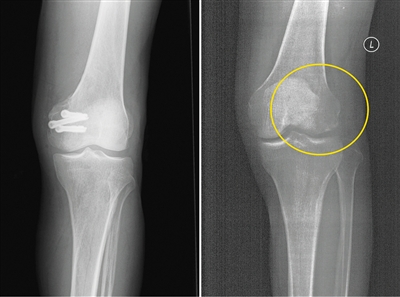

左为使用金属螺钉后拍摄的影像,右为使用蚕丝螺钉后拍摄的影像。受访者供图

在长期的临床应用过程中,金属材料逐渐显现出三大缺陷:一是金属内固定往往需要二次手术取出,大大增加了患者的痛苦及经济负担。二是金属的力学强度远远超过骨骼,导致应力遮挡,影响骨折愈合。此外,使用部分金属材料术后无法进行CT和磁共振拍摄;即使钛合金材料可以进行检查,也存在明显的伪影,螺钉周边模糊一团,严重影响影像观察的效果。

今年5月,患者张强(化名)不慎扭伤,造成左股骨远端骨折。由于骨折部位靠近关节面,使用金属螺钉固定时应力过大,会影响骨折愈合;1年后还需要手术将金属螺钉取出,可能造成二次创伤。患者入院之后,团队经过详细探讨病情、细致阅片后认为,该患者符合可降解蚕丝螺钉固定的适应证。术中团队对该患者使用可降解蚕丝螺钉固定骨折块,术后的CT片中没有任何伪影,可以清晰地看到骨折块已经完全复位,并且解除了患者二次手术取出螺钉的负担和困扰。